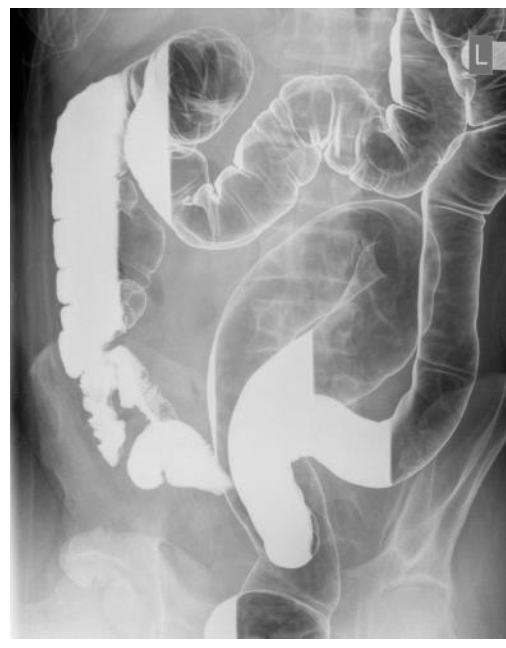

של חולה קרוהן MRI בתמונה

מה החצים מסמלים?

גדושים SMA חץ אדום- הענפים של ה

חץ כחול- דופן המעי עבה ומלאה מים

חץ כתום- כיבים

בנוסף ניתן לראות קשריות לימפה נפוחות שמעידות על דלקת (?)